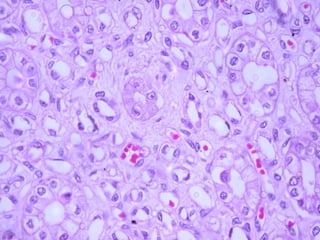

El  corpúsculo renal  constituye el comienzo de la nefrona y está compuesto por un  glomérulo,  que es un ovillo capilar formado por 10 a 20 asas capilares, rodeado por una estructura epitelial bilaminar caliciforme llamada  cápsula renal  o  cápsula de Bowman.  Los capilares glomerulares reciben la sangre desde una  arteriola aferente  y  la envían a una  arteriola eferente  que luego se ramifica para formar una red capilar nueva que irriga los túbulos renales.

Aparato de filtración del riñón El corpúsculo renal es redondeado y tiene un diámetro promedio de 200  μ m. Consiste en un ovillo capilar glomerular y las hojas epiteliales visceral y parietal de la cápsula de Bowman circundante. El aparato de filtración, encerrado por la hoja parietal de la cápsula de Bowman, tiene tres componentes:

Aparato de filtración del riñón Endotelio de los capilares glomerulares,  que posee numerosas fenestraciones. Membrana basal glomerular  (MBG), una lámina basal gruesa (300 a 350 nm) que es el producto conjunto del endotelio y los podocitos, las células de la hoja visceral de la cápsula de Bowman. Hoja visceral de la cápsula de Bowman,  que contiene células especializadas llamadas  células epiteliales viscerales  o  podocitos.

Mesangio El corpúsculo renal contiene un grupo celular adicio-nal que consiste en las  células mesangiales. Estas células y su matriz extracelular constituyen el  mesangio. Las células mesangiales tienen una posición similar a la de los podocitos porque están encerradas por la lámina basal de los capilares glomerulares y se encuentran incluidas en una matriz mensagial laxa que ellas mismas producen.